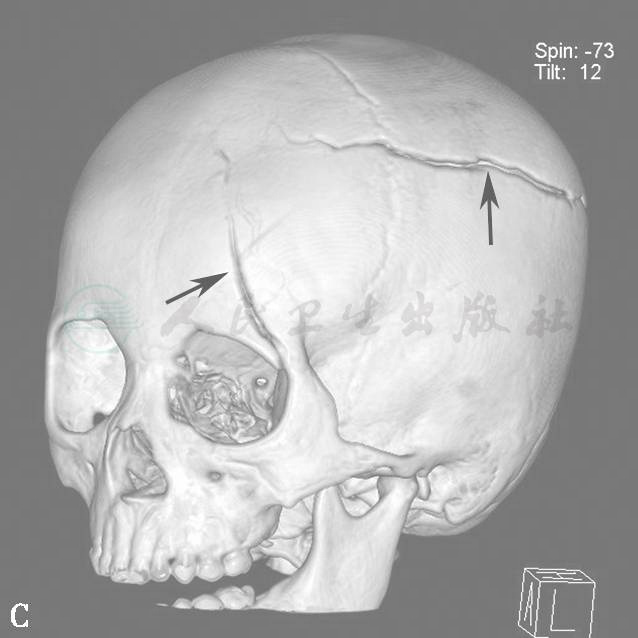

图15为颅脑外伤出血伴骨折病例。

图15  外伤后颅内出血(箭)

A.脑组织窗;B.骨窗;C.VR重建